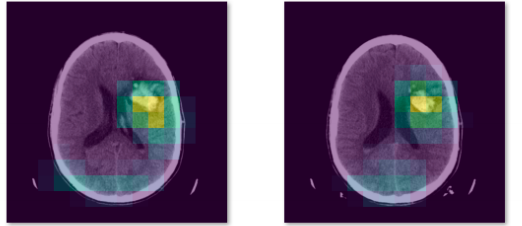

但是你需要改一改,怎么改呢 ? 我举个栗子:你可以做疾病分类,网上有很多的开源数据集,判断一张图片是猫还是狗和判断一张图片有没有病本质上是一样的。

如果你想搞一些花里胡哨的东西,可以借助注意力机制把病灶找出来,最终的效果就是:输入一张医疗图片,会输出这张图片患病概率,而且把这张图片上的病灶高亮出来。

640-15-1

开源数据集:CQ500

对于一个本科毕业设计来说,我觉得做到这种程度足够了,如果你看不懂我刚刚说的技术名词,把我刚刚推荐的吴恩达深度学习教程看完,你就能明白了。